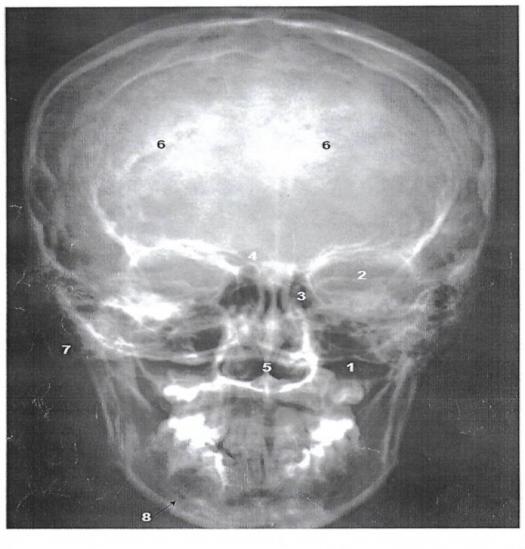

39. The part number 6 represents :

Explanation

The part number 6 represents the lambdoid suture. The lambdoid suture is a dense, fibrous connective tissue joint that connects the parietal bones of the skull to the occipital bone at the back of the head. It is named after its shape, which resembles the Greek letter lambda (Λ). The lambdoid suture helps to provide stability and strength to the skull, as well as allowing for some flexibility during childbirth.